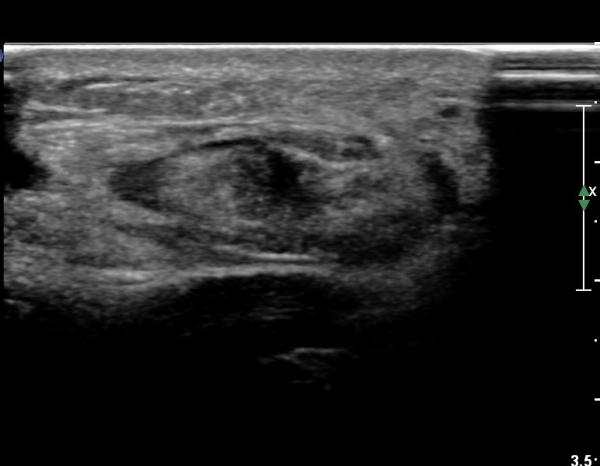

¾ÆÅ³·¹½º°Ç Á¾´Ü¸é°Ë»ç¿¡¼ ¾ÆÅ³·¹½º°Ç Àú¿¡ÄÚ ºÎÁ¾, ¿¬°á¼º ¼Ò½Ç, °ÇÁÖÀ§ ¼ö¾×Àú·ù ¼Ò°ßÀ» º¸ÀÓ(»çÁø 2, 3, 4, 5).

¾ÆÅ³·¹½º°Ç Ⱦ´Ü¸é°Ë»ç¿¡¼ ¾ÆÅ³·¹½º°Ç Àú¿¡ÄÚ ºÎÁ¾, ¿¬°á¼º ¼Ò½Ç, °ÇÁÖÀ§ ¼ö¾×Àú·ù ¼Ò°ßÀ» º¸ÀÓ(»çÁø 6, 7, 8).